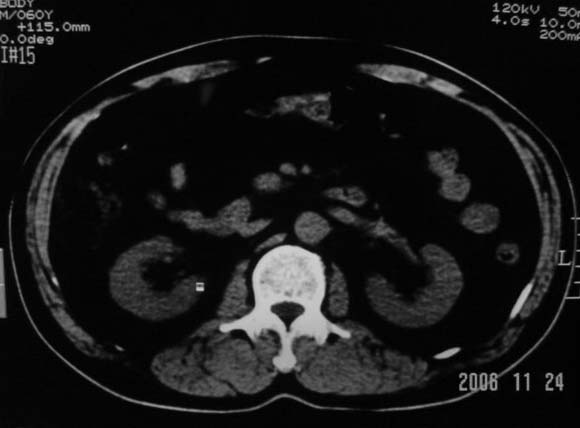

标题: CT5395:男、60岁,皮肤、巩膜黄染伴上腹部疼痛20天 [打印本页]

标题: CT5395:男、60岁,皮肤、巩膜黄染伴上腹部疼痛20天

劳烦各位老师看一下最后一幅箭头指的地方是不是胆总管结石.ct值约63hu.

感觉不是结石可能,与上一层面联系应该是门脉区影像,图像显示不佳,胆总管显示不清[特别是胰头以上段],目前影像只能说肝内外胆管扩张,胰管扩张,胆囊扩大。提示胆总管远端梗阻。可考虑肿瘤或结石所致

胆总管内结节状高密度灶,边缘隐约可见低密度环绕,首先考虑结石伴肝内胆管扩张; 2、胆囊增大,胆囊炎

肝内外胆管及胰管均示有扩张,胆囊增大.提示胆总管远端梗阻,可考虑肿瘤或结石或肿瘤伴结石,建议强化扫描

1.肝内外胆管扩张,楼主箭头所示处多系结石.

2.图象太黑,窗位太高,窗宽太窄,解剖结构显示欠佳 .